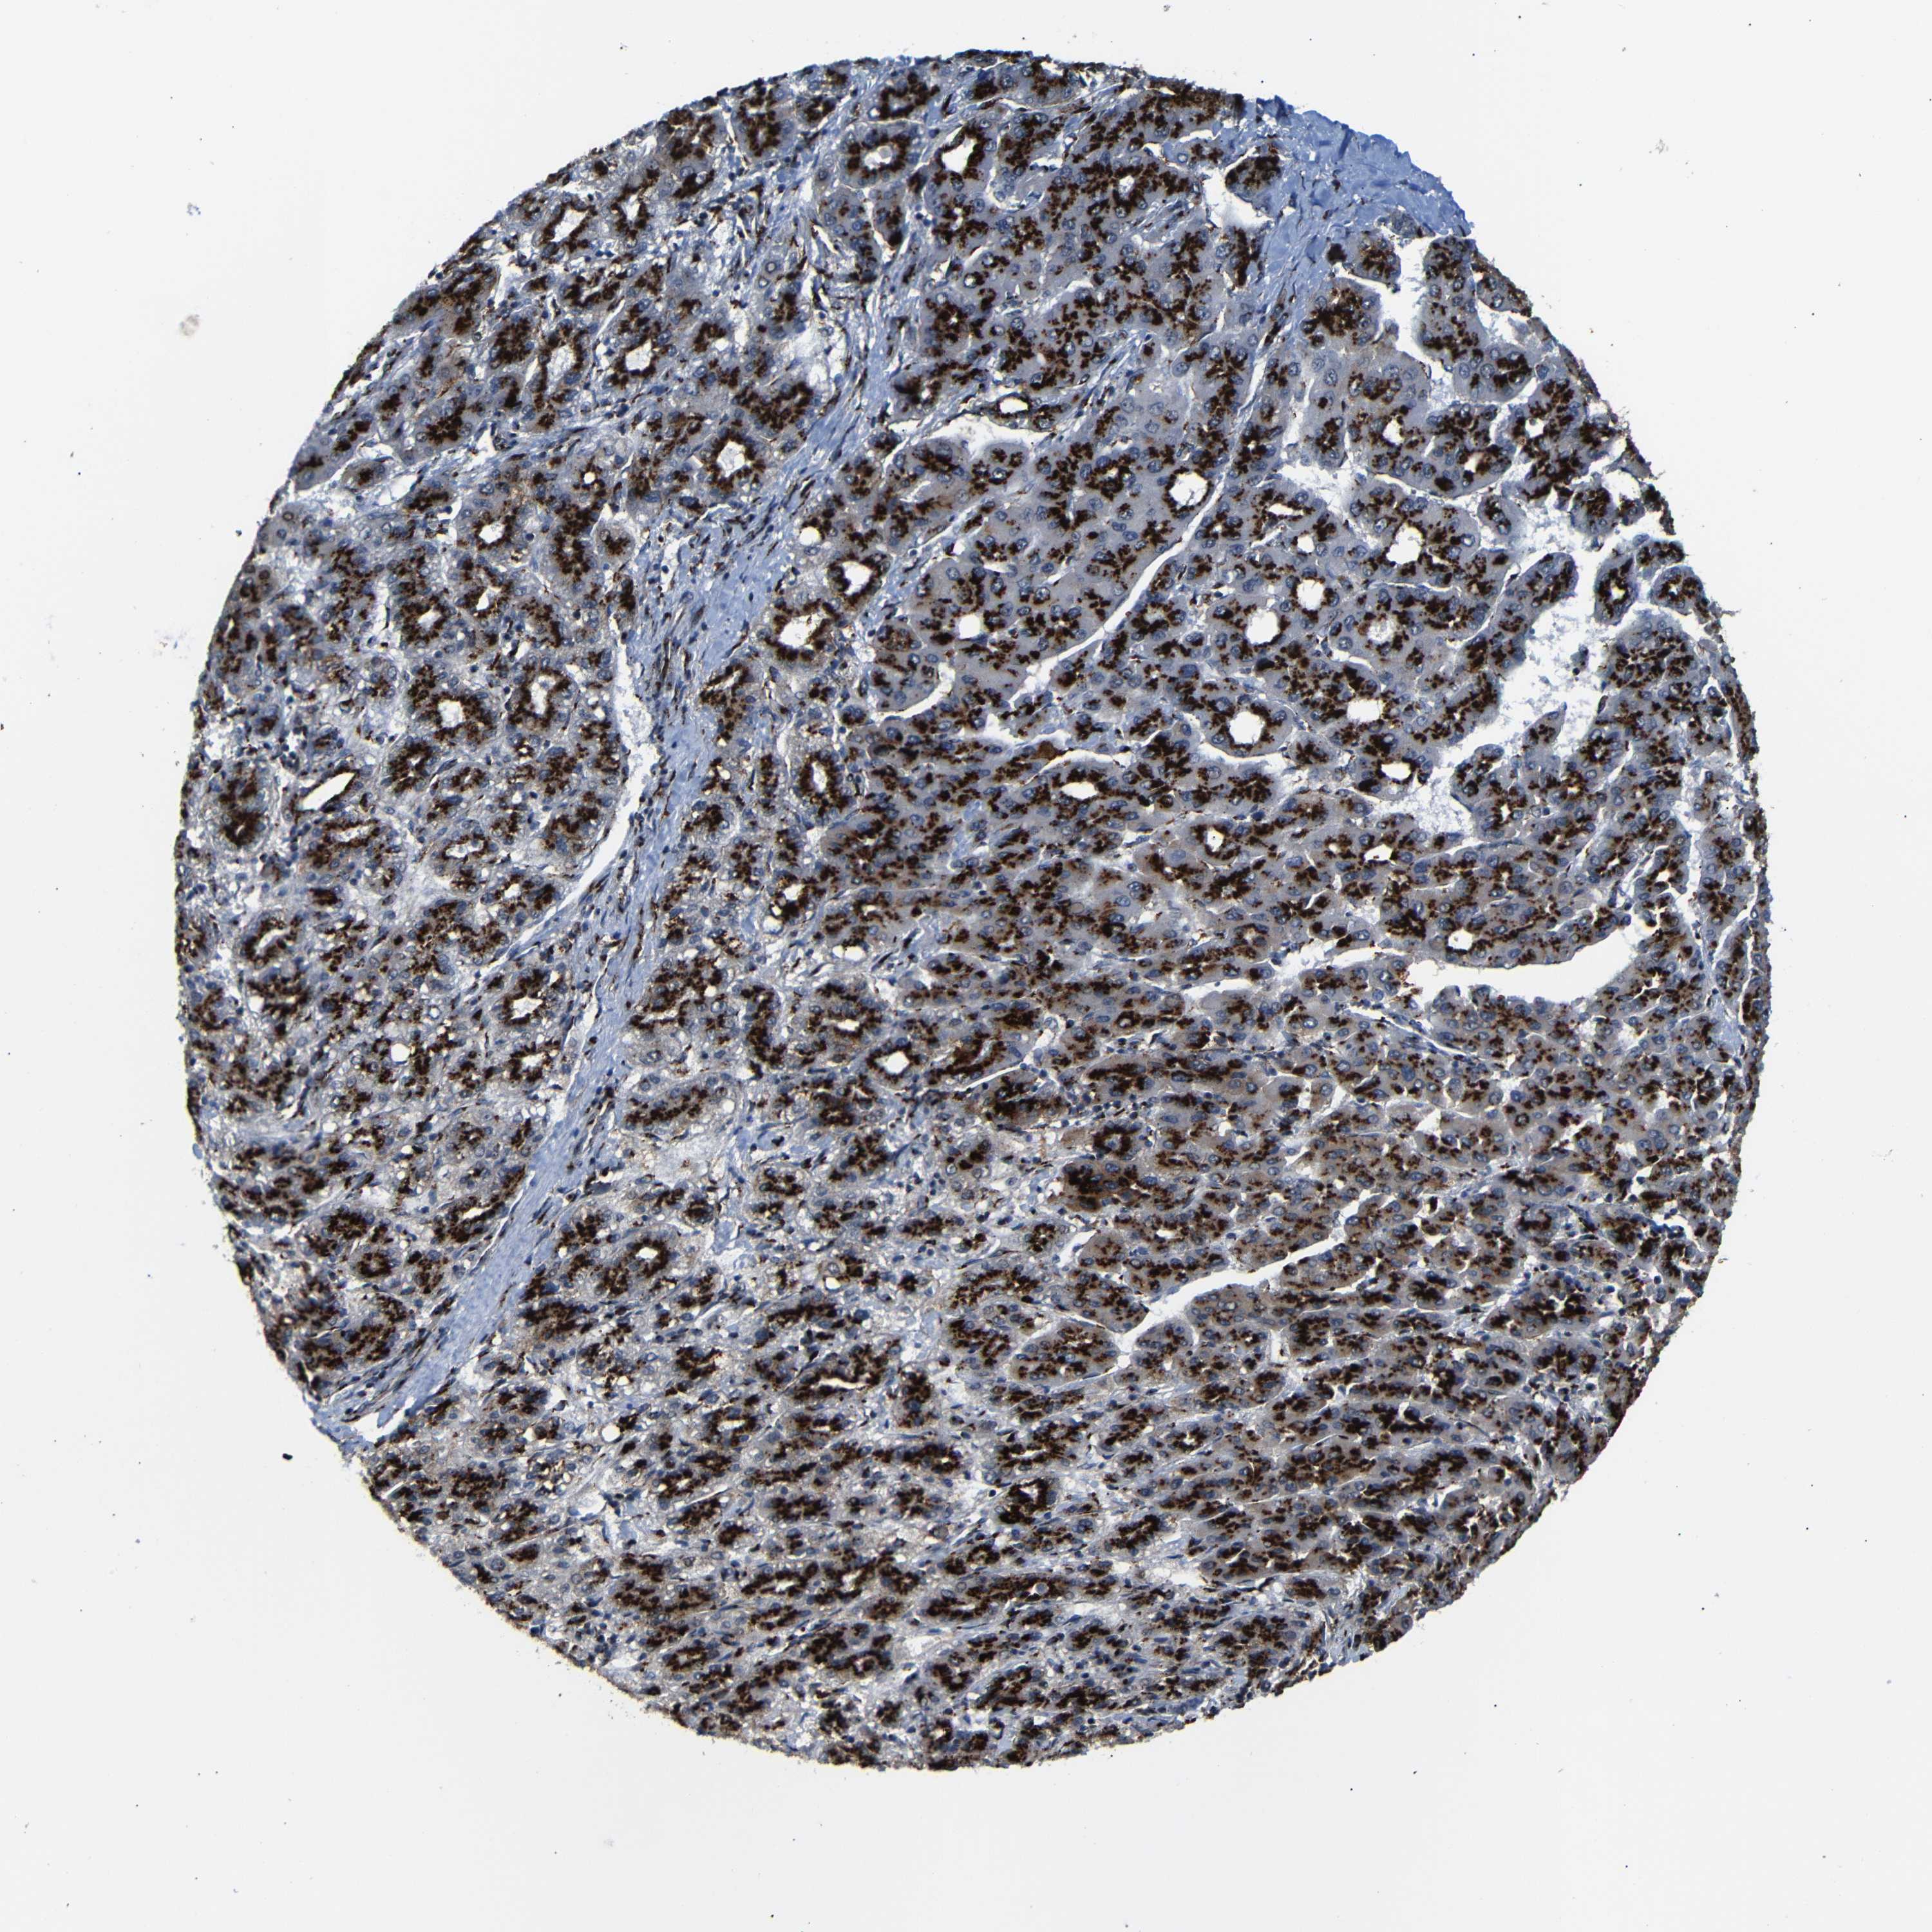

LIVER CANCER - Protein expressioni

A mouse-over function shows sample information and annotation data. Click on an image to view it in a full screen mode. Samples can be filtered based on level of antibody staining by selecting one or several of the following categories: high, medium, low and not detected. The assay and annotation is described here.

Note that samples used for immunohistochemistry by the Human Protein Atlas do not correspond to samples in the TCGA dataset.

Antibody stainingi

Antibody staining in the annotated cell types in the current human tissue is reported as not detected, low, medium, or high, based on conventional immunohistochemistry profiling in selected tissues. This score is based on the combination of the staining intensity and fraction of stained cells.

Each image is clickable and will lead to virtual microscopy that enables deeper exploration of all samples and also displays staining intensity scores, fraction scores and subcellular localization as well as patient and tissue information for each sample.

Antibody HPA012609

Antibody HPA012723

Antibody CAB011489

Staining

High

Medium

Low

Not detected

Intensity

Strong

Moderate

Weak

Negative

Quantity

>75%

75%-25%

<25%

None

Location

Nuclear

Cytoplasmic/membranous

Cytoplasmic/membranous,nuclear

Cholangiocarcinoma

Carcinoma, Hepatocellular, NOS